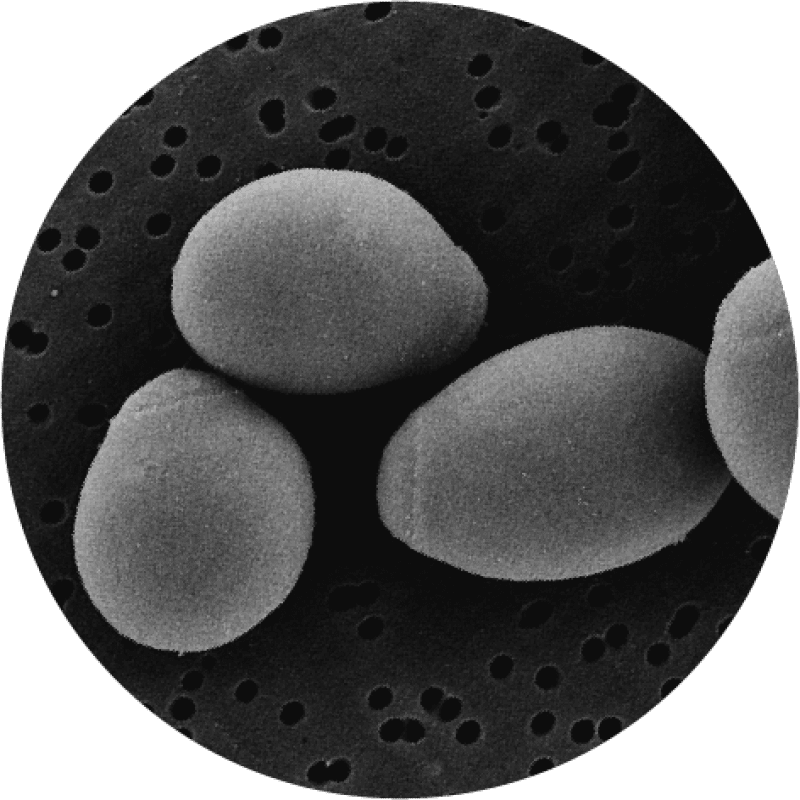

Saccharomyces boulardii under the microscope

Saccharomyces boulardii is unique in this database of the world's best probiotic strains, in that it is a non-pathogenic, transient (non-colonising) yeast, originally extracted from the lychee fruit, rather than a bacteria. It is important to note, however, that it is genetically and functionally different from the well-known pathogenic Candida family of yeasts. It was originally classified as a separate species but, after much laboratory testing, it was shown to have certain genomic and structural similarities to Saccharomyces cerevisiae and so is now classified as part of this species. That being said, S. boulardii is a unique microorganism and has vastly different strain-specific properties to other yeasts in the same S. cerevisiae species, in the same way that different strains of bacteria may have completely different actions and properties to other strains within the same species. For more information on the classification of Saccharomyces boulardii, please read our in-depth article.